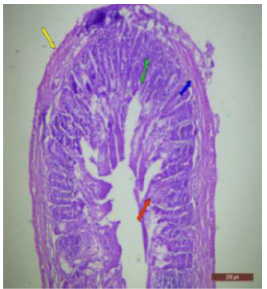

The ileal mucosa of control rat was built up of numerous folds forming the villi, through which connective tissue of the lamina propria containing tubular glands i.e., crypts of Leiberkühn were present (Figure 18). The epithelial lining of the villi was composed of Paneth cells and intestinal glands (Figure 19). In fluorotic rats, there were abnormal shaped, damaged and broken villi with bulbous tips. Lymphatic dilation and haemorrhaged in lamina propria were also seen (Figure 20). In the ileal mucosa, prominent inflammation, distortion of crypts with shredded cells inside the crypts were visible (Figure 21). Swollen and necrotic crypts were present (Figure 22). The ileal tissue showed disruptions in the normal mucosal architecture with signs of villous atrophy and cell infiltration (Figure 23). Lymphatic infiltration was prominent and numerous enlarged lymph nodules appeared in lamina propria of villi. There were ill-defined cell boundaries, vacuolated cytoplasm and pyknotic nuclei (Figure 24).

Figure 20: T.S. of ileum of rat treated with 600 mg NaF/kg b.w./day for 40 days showing broken villous and necrotic crypts (↑).H&E × 100.

Figure 21: T.S. of ileum of rat treated with 600 mg NaF/kg b.w./day for 40 days showing inflammation (↑) in the mucosa. H&E × 100.

Figure 22: T.S. of ileum of rat treated with 600 mg NaF/kg b.w./day for 40 days showing swollen (↑), broken villus and necrotic tips (↑). H&E × 100.

Figure 23: T.S. of ileum of rat treated with 600 mg NaF/kg b.w./day for 40 days showing disrupted mucosal structure. H&E × 40.

Figure 24: T.S. of ileum of rat treated with 600 mg NaF/kg b.w./day for 40 days showing abnormalities in the lymph nodes (↑). H&E × 100.